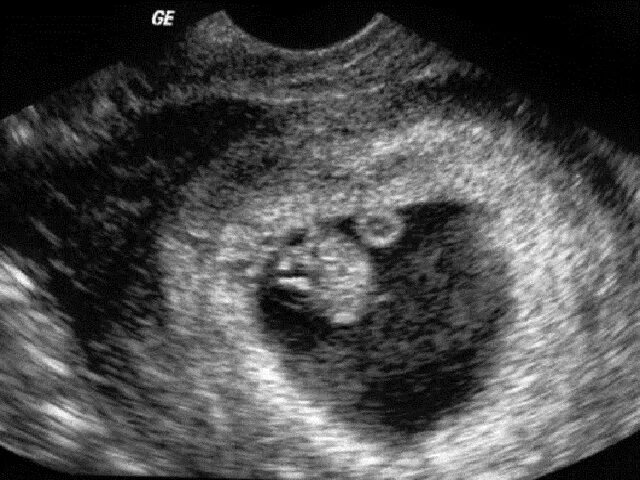

Плодное яйцо желточный мешочек